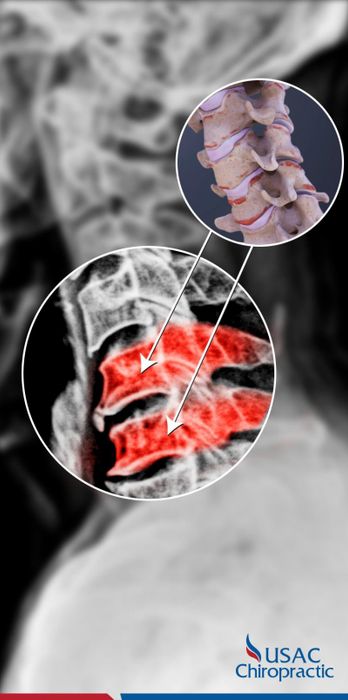

4. USAC Chiropractic

CallAs one of the leading American-standard musculoskeletal treatment centers in Vietnam, USAC is proud to own a system of clinics stretching from North to South with the most advanced equipment. Moreover, all doctors at USAC are from foreign countries with highly developed medical systems such as the USA, Europe, and Japan. This is the factor that helps USAC Chiropractic become confident and strong in the hearts of hundreds of thousands of patients. USAC Chiropractic has many years of strength in musculoskeletal diseases, focusing recently on developing solutions for general spine issues and spinal degeneration in particular.

'Selling trust and conviction' is the general mentality of patients when they know that USAC Chiropractic treats spinal degeneration, disc herniation with the Bone Power X4 protocol, guaranteeing no medication, no surgery, yet still reducing pain quickly. The Bone Power X4 protocol is designed and treated by the Joint Council of American and European Orthopedic Physicians with over 25 years of experience, providing 4 times more effective and faster treatment than other conventional methods, helping: Stop acute pain, adjust misaligned vertebrae, restore, restructure the entire spine, maintain, preserve a healthy spine.